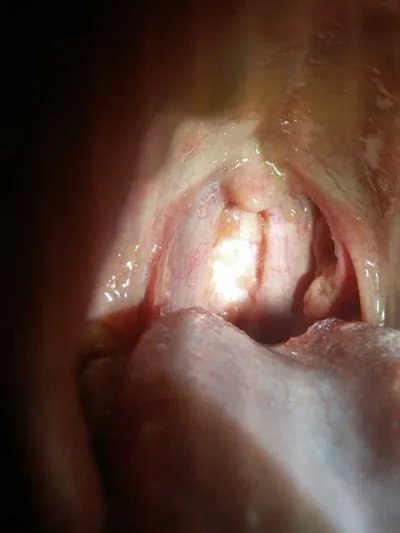

发绀 是缺氧的典型表现。

当动脉血氧饱和度低于90%时,可在口唇、指甲出现发绀;